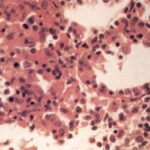

Histopathology. The histopathologic appearance itself is not sufficiently specific to exclude other diseases . The classical description of the disease is that it evolves through three stages. In the first phase, there is only erythema and induration clinically. Histologically, acute inflammation is found in the fat lobules with degeneration of fat cells and an infiltrate of neutrophils, lymphocytes, and macrophages. The second phase has an infiltrate discretely localized to the fat lobules, consisting mainly of macrophages, foam cells, and extracellular lipid droplets. In some cases, the lesions perforate the skin surface and discharge a sterile, oily liquid. The third phase |

Differential Diagnosis. The histologic appearance of Weber-Christian disease is most distinctive in the second phase, when there is an infiltration by lymphocytes and macrophages between fat cells that is discretely localized to the fat lobules. Erythema nodosum with unusual predominance of neutrophils can resemble the early phase of Weber-Christian disease, except for the localization of erythema nodosum primarily in the septa and WeberChristian mainly in the lobules. Likewise, AA T deficiency can resemble early Weber-Christian disease except that the neutrophilic infiltrate in AAT deficiency usually affects the dermis and septa as well as the lobules. Subcutaneous fat necrosis of pancreatic disease can produce some of these findings but usually can be recognized by the extensive necrosis and deposition of bluish calcium precipitates with fatty acids. Histiocyticcytophagicpanniculitis has some of the clinical features but histologically has a lymphoid infiltrate with macrophages that |

have ingested sufficient lymphocytes, neutrophils, and eosinophils to be called bean bag cells ). |